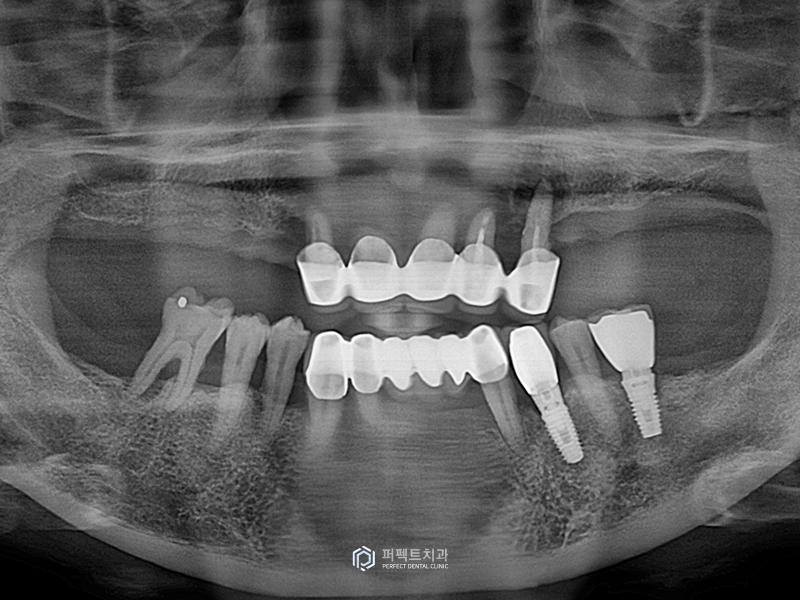

환자분이 처음 내원 하셨을 때 파노라마 엑스레이 사진입니다.

위에 치아는 앞니가 있지만 잇몸뼈가 많이 녹아있어 앞니를 사용하기 힘들고, 임플란트 식립도 할 수 없는 상태였기 때문에 뒤 쪽을 이용해 임플란트를 식립하기로 했습니다.

환자분은 비용적인 부담도 있고 임플란트를 간단하게 하기를 원하셨기 때문에 상악동을 열어서 뼈이식을 하는 과정까지는 원하지 않으셨습니다.

그래서 환자분이 원하시는 대로 방향을 설정하여 계획에 맞게 수술을 하였고 오른쪽 3개, 왼쪽 2개의 임플란트를 심어 밑에 치아까지 저작을 할 수 있도록 간단하게 하는 방법으로 계획을 세웠습니다.